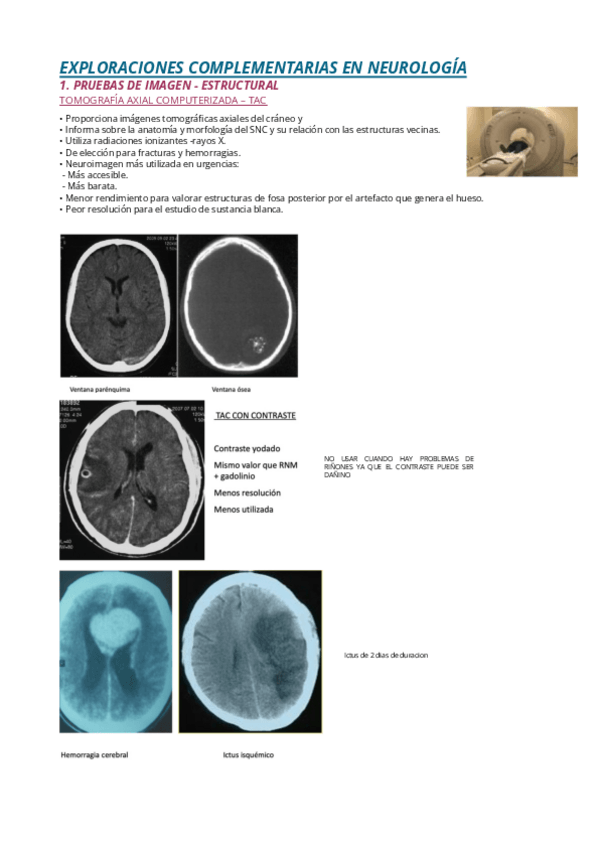

EXPLORACIONES-COMPLEMENTARIAS-EN-NEUROLOGIA.pdf